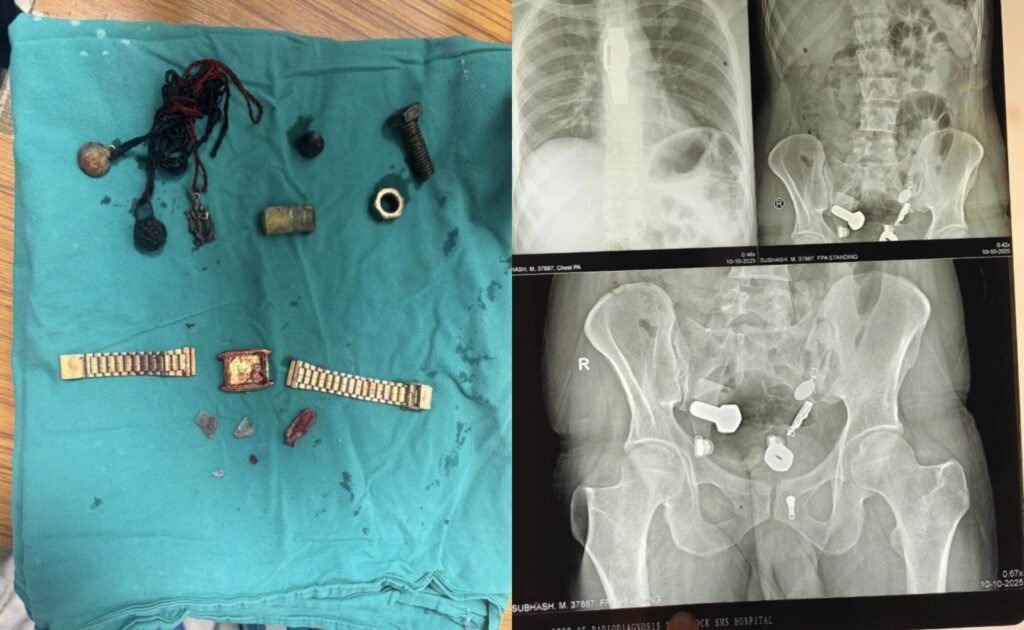

When doctors performed X-ray scans, they were stunned to find a wristwatch lodged in his oesophagus, along with iron fragments, nuts, and bolts trapped in his large intestine.

Initially, medical staff attempted to remove the objects through an endoscopy, but the procedure failed due to the number and size of the items. Surgeons were later forced to perform a three-hour operation to remove everything from his digestive system.

Graphic footage reportedly showed doctors carefully extracting the wristwatch from the man’s abdomen, along with several pieces of metal debris.

The bizarre operation took place on October 9th at Sawai Mansingh Hospital in Jaipur, where the patient had been admitted after his condition worsened.